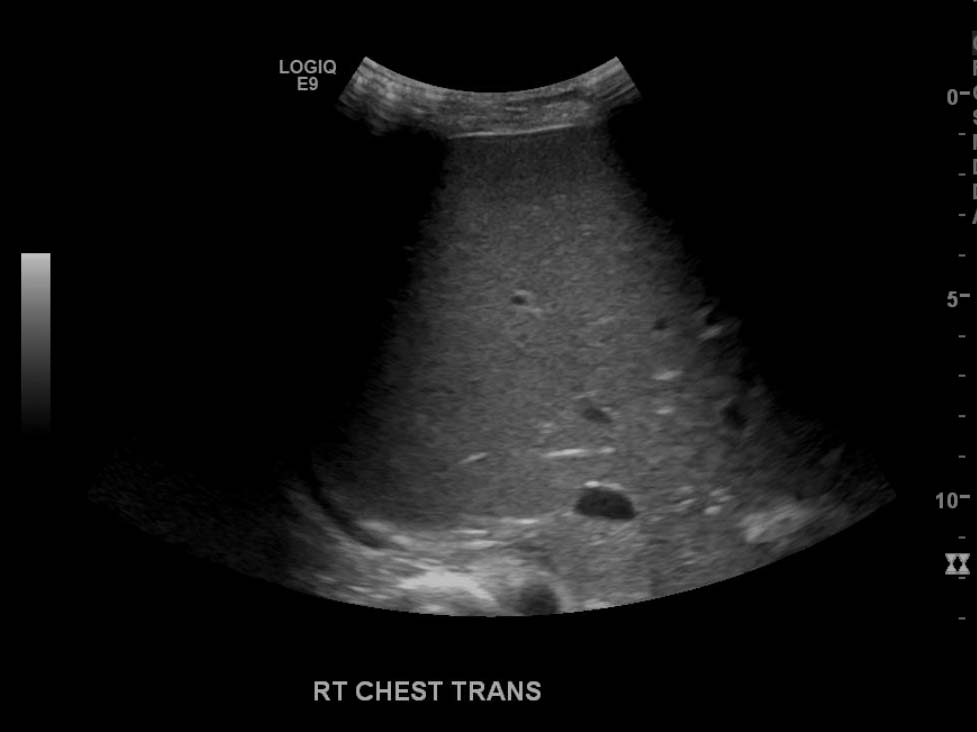

- Large, complex, multiseptated left pleural fluid collection

- No right pleural fluid collection identified

Large, complex, multiseptated left pleural fluid collection with adjacent airspace consolidation, concerning for pneumonia and empyema. No discernible right pleural effusion.

- Simple/transudative pleural effusions should be anechoic on ultrasound

- Worry about a complicated effusion (which may represent empyema, hemothorax, or malignant effusion depending on the clinical scenario) if the fluid collection has hyperechoic areas or if it contains internal septations